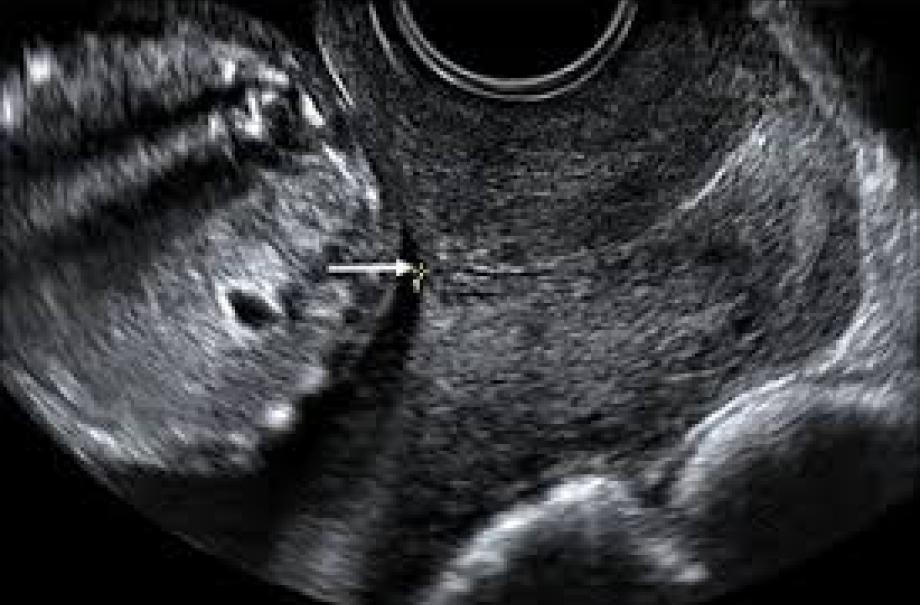

Skan szyjki macicy

- Przezpochwowe skanowanie

- Pomiar szyjki macicy.

- Wykrywanie prezentacji dziecka.

- Potwierdzenie bicia serca.